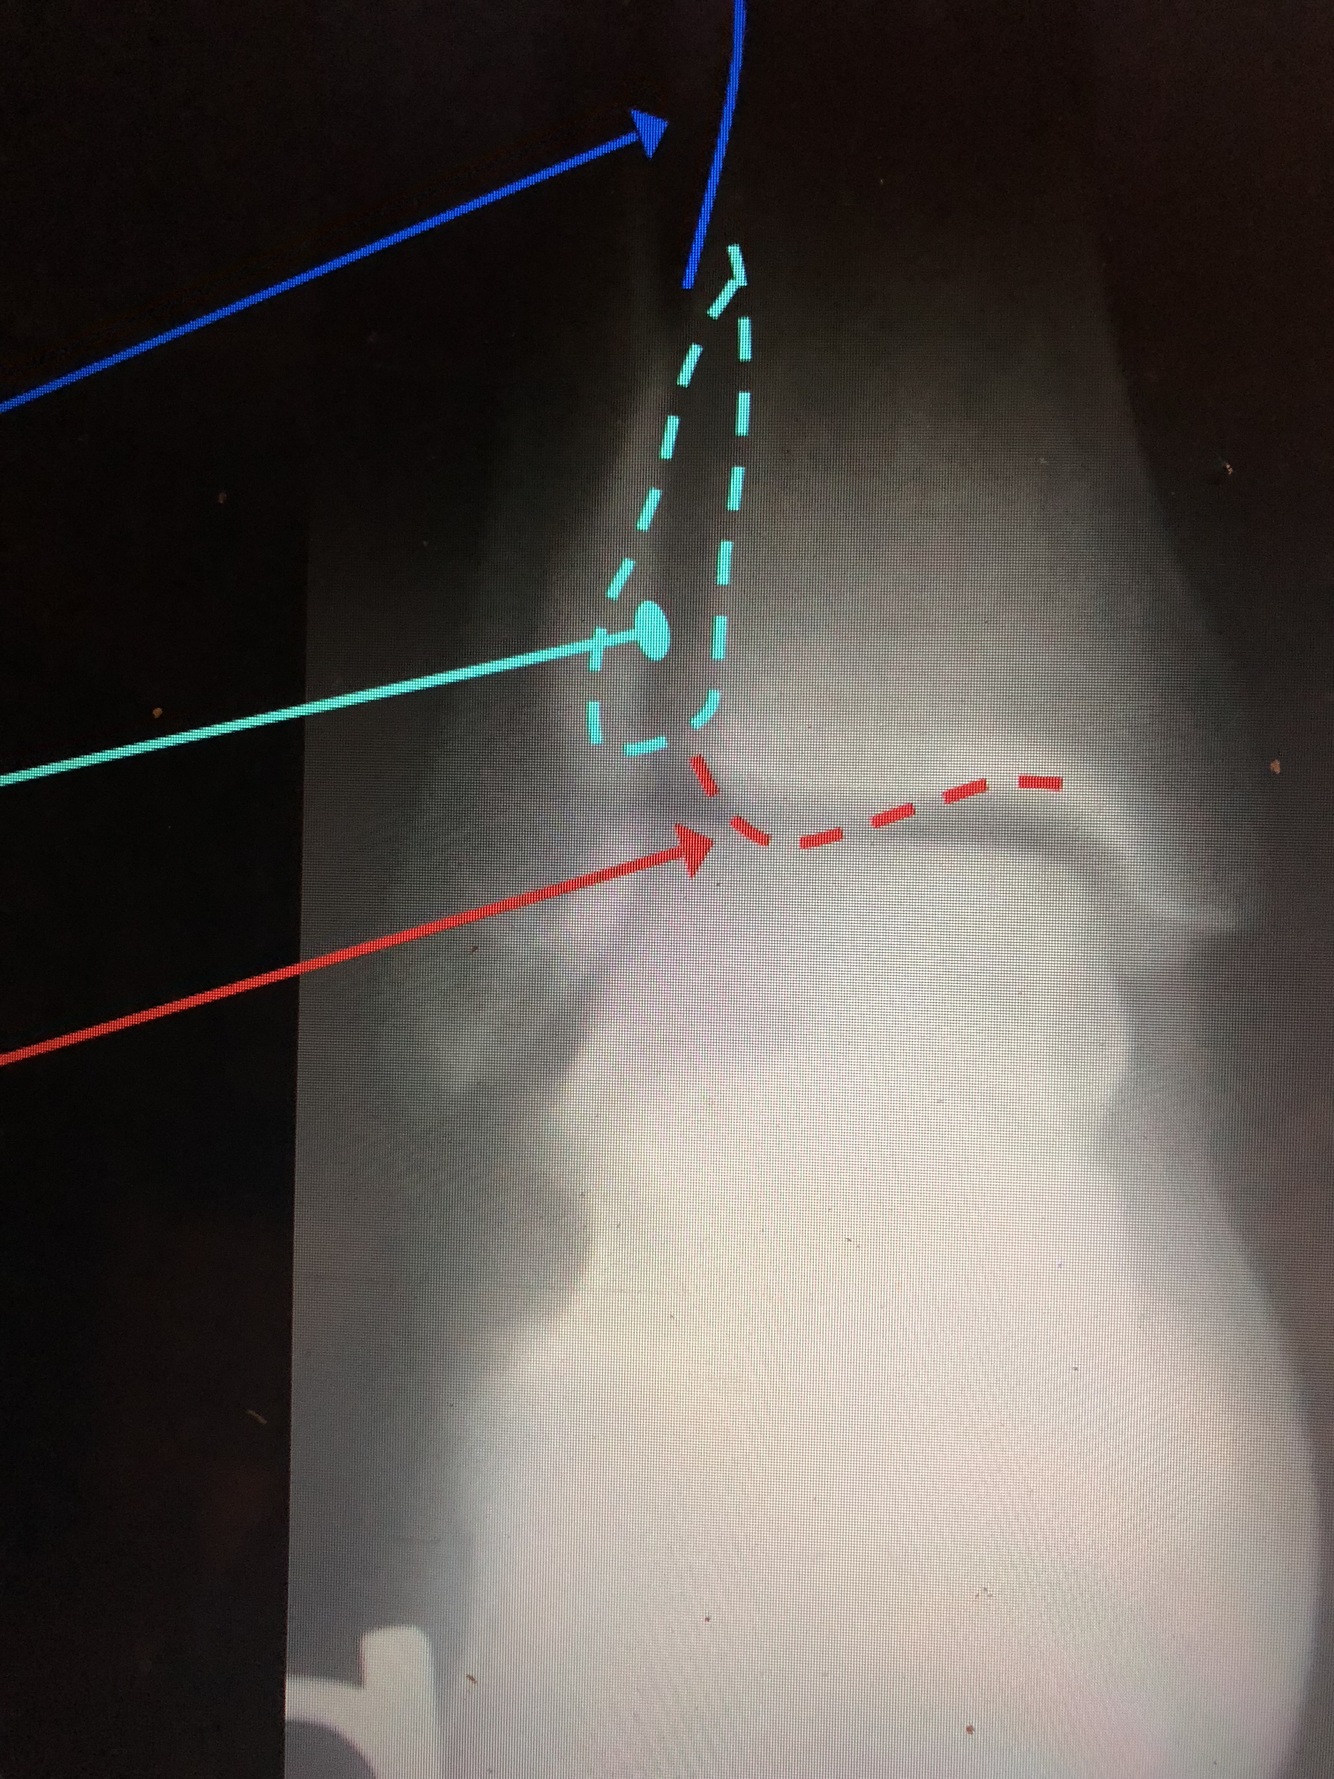

What is the light blue line?

Navicular Tuberosity

What is the dark blue line?

Medial Cuneiform

What bone is yellow?

Talus

What bone is brown?

Navicular

What bone is light green?

Calcaneus

What bone is light blue?

Cuboid

What is the yellow dotted line?

Fibular Notch

Plafond

What is the red line?

Posterior Malleolus

Medial Malleolus

What is the blue line?

Lateral Malleolus